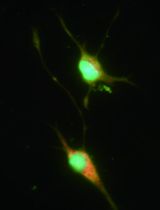

Isolation and ex vivo Expansion of Human Limbal Epithelial Progenitor Cells

人角膜缘上皮祖细胞的分离及体外扩增